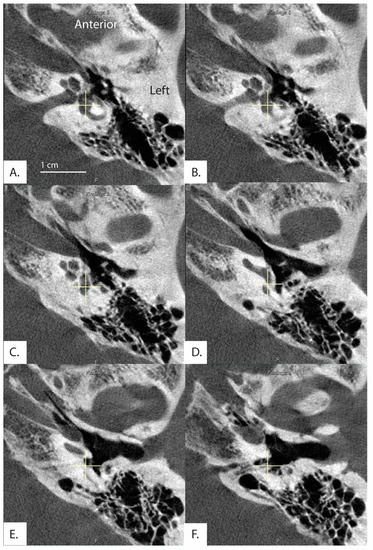

Figure 2.

Images and measurements for all ears with ATVA > 140 degrees are shown. Bächinger et al. software used to measure the ATVA [1]. Some ears use two images to calculate the angle. If the vestibular aqueduct and the vestibule are not visible in a single plane, the software provides an option to use both an image at the level of the vestibule and another image at the level of the distal VA to measure .

In this study 462 (80.8%) ears had angles less than 120 degrees, 96 (16.8%) ears had angles 120 < > 140 degrees, and 14 (2.4%) ears had angles greater than 140 degrees (Table 2). All measurements for ears with angles > 140 degrees are shown in Figure 2. There were no differences among the groups in the ATVA (Figure 3). There were 13 adult patients (4.3%) with > 140 degrees. One patient had ears with > 140 degrees bilaterally. One patient with > 140 degrees had a clinical diagnosis of Meniere’s disease but not in the ear with > 140. The medical records of all individuals meeting the criteria for hypoplastic vestibular aqueduct (>140 degrees) were additionally reviewed. None of the 13 patients had a clinical diagnosis of Meniere’s Disease in the affected ear. These patients were diagnosed with a variety of otologic problems. Of the 14 ears, diagnoses included superior canal dehiscence syndrome (n = 3), thin bone over the superior semicircular canal (n = 1), intracochlear schwannoma (n = 1), otosclerosis (n = 1), or asymptomatic/presbycusis without associated symptoms of Meniere’s disease (n = 7). Images were reformatted in the planes of both the superior SCC and the posterior SCC and orthogonal to these planes. For the affected ears, imaging was interpreted by the radiologist as normal (n = 8), to have a dehiscent superior SCC (n = 3) to have thin bone overlying the superior (n = 1) or posterior (n = 2) semicircular canals. Other incidental findings include a prior transverse sinus stent (n = 1), bony exostoses of the external auditory canal (n = 1), and a prior right mastoidectomy performed for superior canal plugging (n = 1). None of the patients had a dehiscence of the posterior SCC. One ear had episodic aural fullness and two episodes of spinning vertigo, but with a high frequency hearing loss on pure tone audiometry, meeting the diagnosis of probable Meniere’s disease.

Additionally, in 30 patients, the distal vestibular aqueduct in the region of the operculum of one ear was determined too difficult to clearly visualize and measure when reformatted in the plane of the horizontal semicircular canal, even in these high resolution CT images. Figure 5 shows a patient whose distal vestibular aqueduct was unidentifiable in the image stack. Figure 6A–D demonstrates how although the image was captured in the plane of the horizontal semicircular canal, the distal portion of the vestibular aqueduct is not visible and takes a complicated trajectory through the bone. In addition, often the vestibular aqueduct is visualized as a small wedge-shaped figure (Figure 6A–D) that may be a representation of the vestibular aqueduct directly parallel to its entering the temporal bone rather than a visualization of the vestibular aqueduct perpendicular to its travel through the bone. This is partially accounted for by the software as there is an option to use both an image at the level of the vestibule and if the distal aqueduct is not visible in that image, another image at the level of the distal VA to measure .